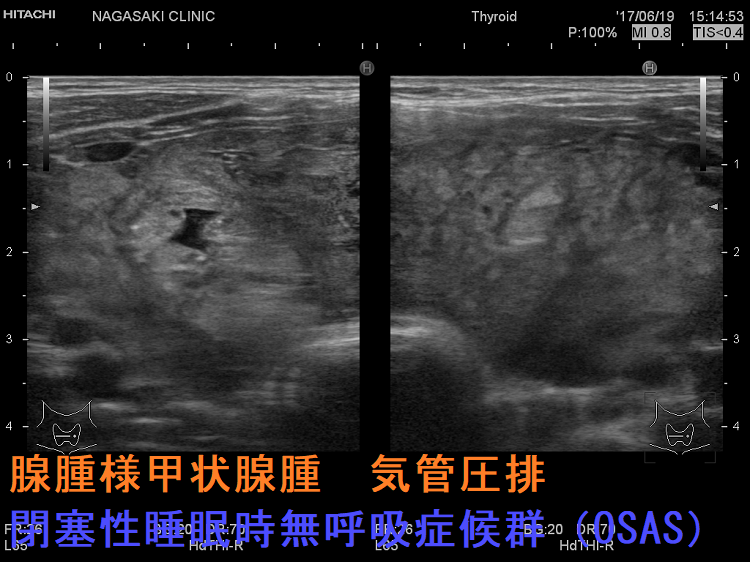

腺腫様甲状腺腫

腺腫様甲状腺腫でも咽喉頭圧排と浮腫により、閉塞性睡眠時無呼吸症候群(OSAS)を引き起こします。甲状腺全摘出で改善(J Laryngol Otol. 2012 Feb;126(2):190-5.)。

ケース②